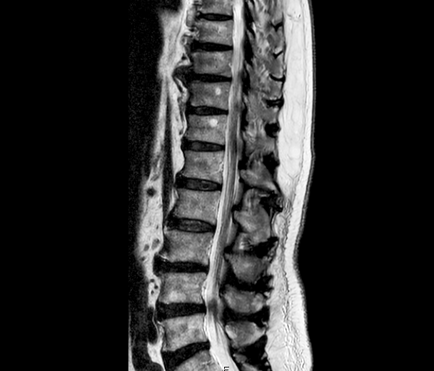

脊柱管狭窄症

脊柱管 上関節突起 骨棘 椎間板変性

整形外科にてレントゲン、MRI検査をし脊柱管狭窄症と診断。牽引、電療、投薬治療にて改善せず来院される。

ただし、多くの慢性腰痛の患者さんの画像を確認させていただくと、何かしら腰椎周辺に問題があることが多く確認できます。

慢性的に腰痛があるのであれば、一度MRI検査などをして、ご自身の痛みの出ている部分、腰痛であれば腰椎を確認していただくことが望ましいです。